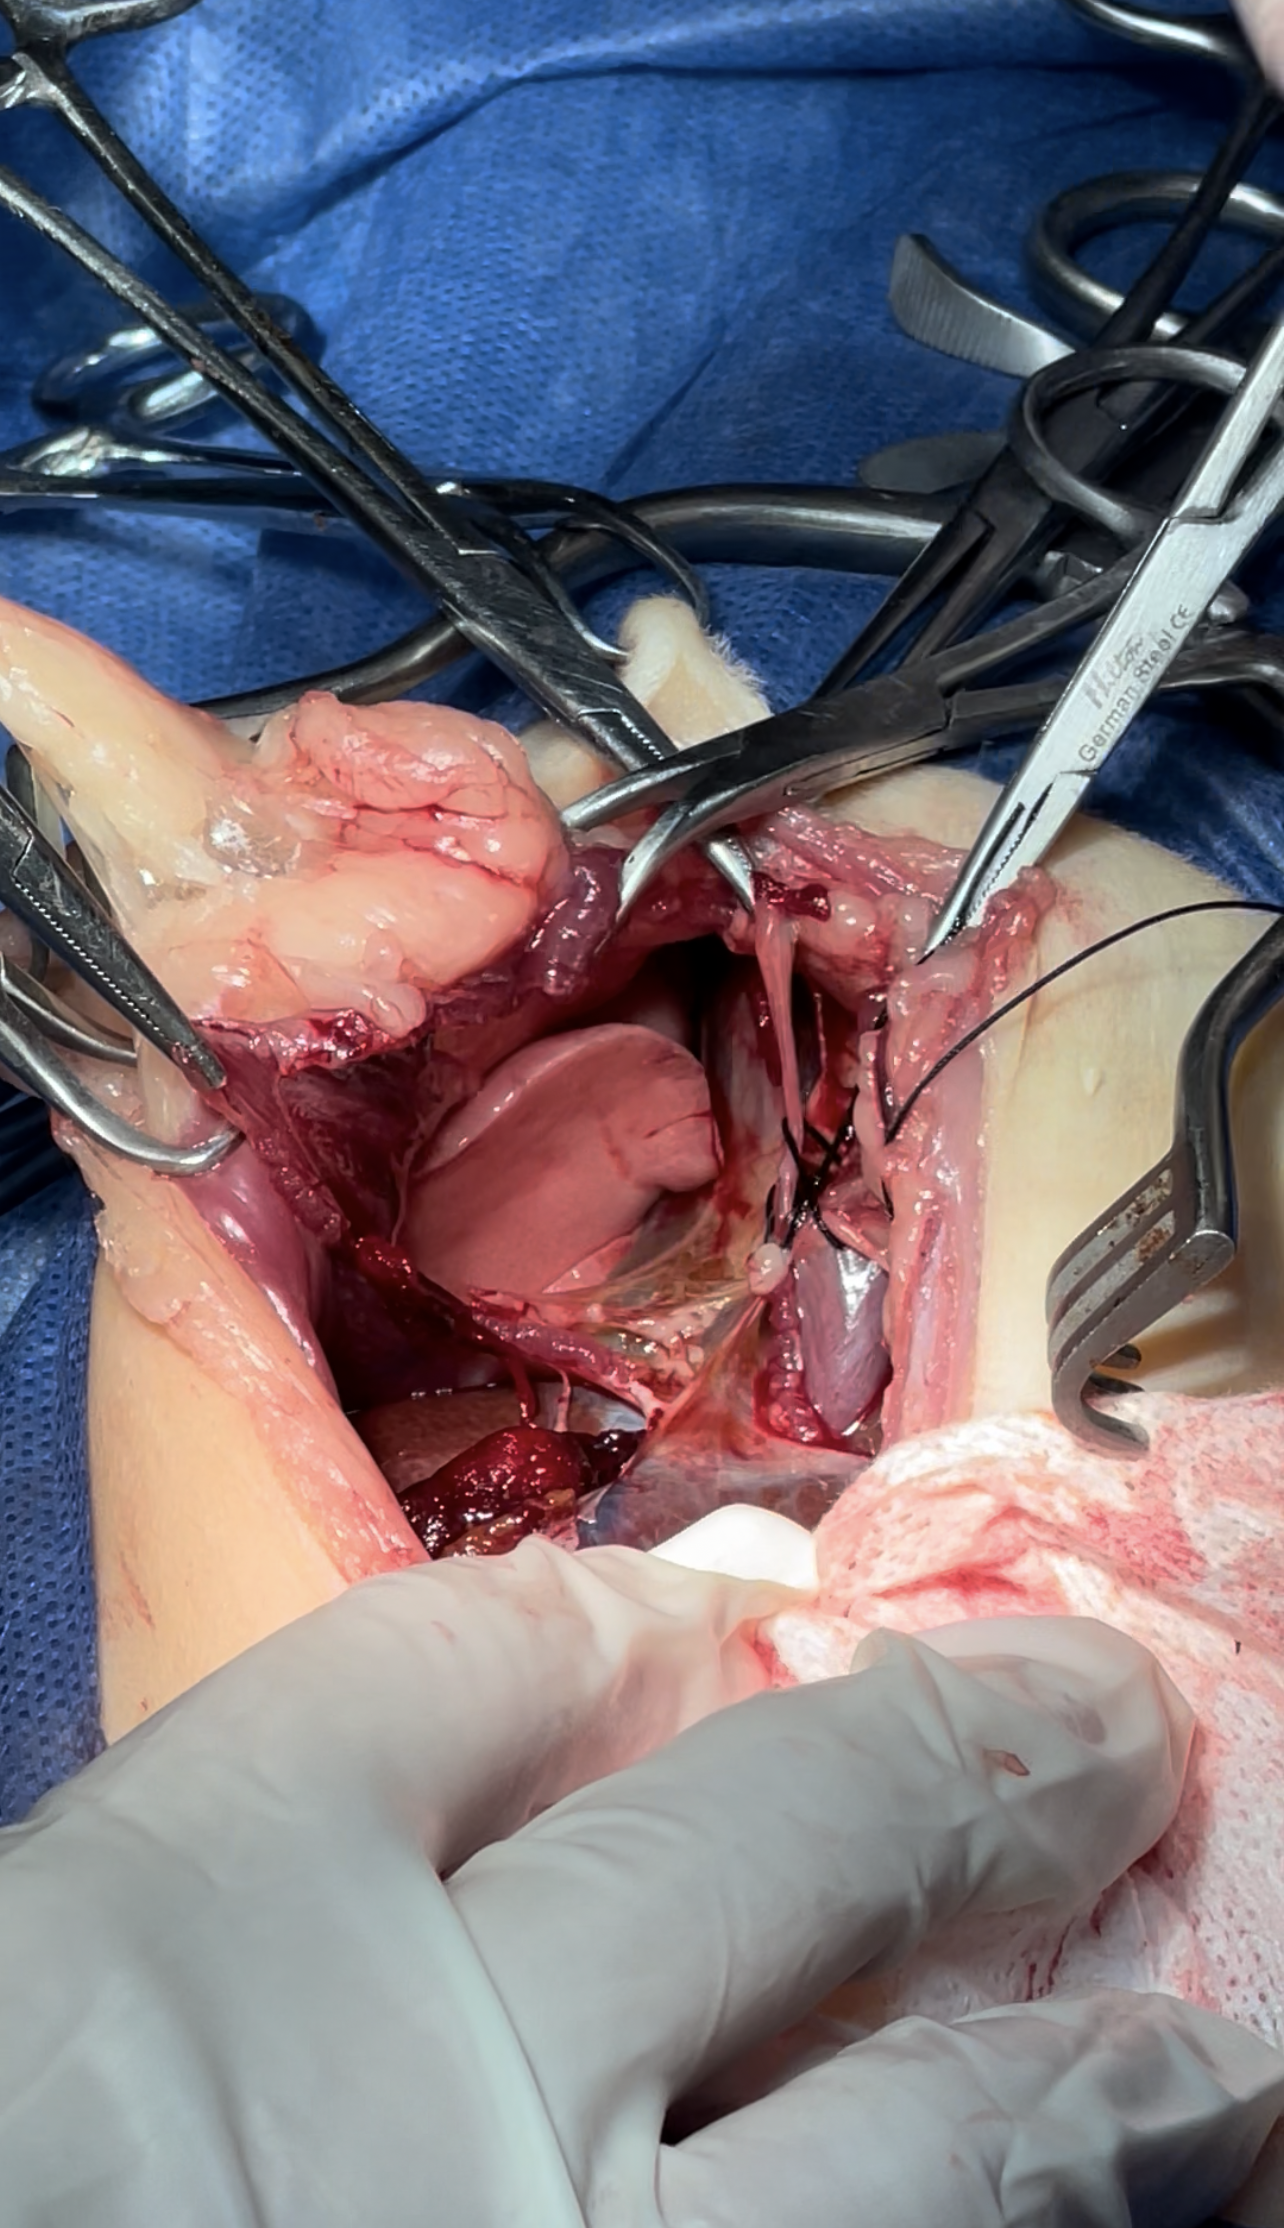

Dissection of the intraabdominal adhesive part of the live

Lacerations while dissection compressed with Gelfoam to minimize the parenchymal injury